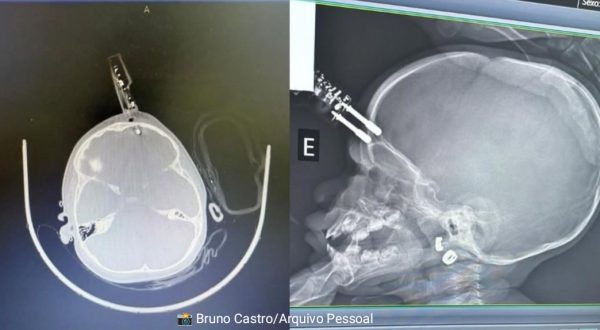

Bebê de 1 ano passa por cirurgia de urgência após acidente doméstico

Uma bebê de 1 ano precisou ser submetida a uma cirurgia de urgência após um acidente doméstico registrado na terça-feira (13), em Divinópolis,...